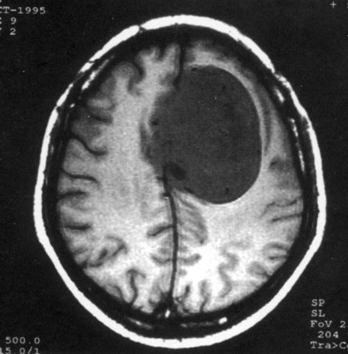

问题 病历摘要:??患者女性,37岁。大便时突起炸裂样头痛3小时,伴喷射样呕吐。既往体健。体检:T37.5℃,BP145/90mmHg,R20次/分,P85次/分。神志清楚,颅神经检查无异常,颈强直,克、布氏征(-),四肢肌力、肌张力正常,病理征(-)。 目前治疗颅内动脉瘤的主要方法有哪些?

选项 A.r刀 B.开颅动脉瘤夹闭术 C.开颅载瘤动脉夹闭及动脉瘤孤立术 D.开颅动脉瘤包裹术 E.血管内动脉瘤栓塞术 F.X刀 G.动脉瘤颈结扎术 H.颈动脉结扎术

答案 BCDE